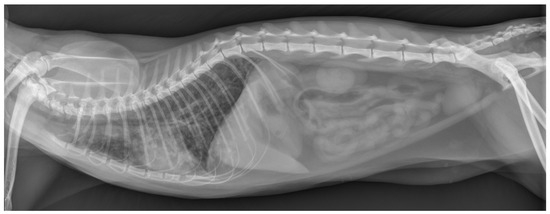

Abdominal ultrasonography revealed no abnormalities of the liver, spleen, kidneys, adrenal glands, pancreas, liver, gall bladder, stomach, and intestines, but mild mesenteric lymphadenopathy likely reflected a reactive change. A laterolateral thoracic radiograph was performed and showed a generally reduced opacity of the lung fields with a mixed bronchointerstitial to alveolar lung pattern, a poorly delineated cardiac silhouette and a mildly increased vertebral heart size (VHS) of 9.4 (normal right lateral VHS: <8.1) (Figure 1).

Figure 1. Thoracic radiograph at the time of presentation. This laterolateral view shows a generalized mixed bronchointerstitial to alveolar lung pattern, resulting in a decreased delineation of the cardiac silhouette.

Diagnostic imaging revealed a normal appearance of abdominal organs (i.e., liver, spleen, kidneys, adrenal glands, pancreas, liver, gall bladder, stomach, and intestines) but marked alterations of the intrathoracic respiratory system (i.e., all lung fields). Specifically, thoracic radiographs at the time of presentation showed a mild generalized alveolar lung pattern with air-bronchograms superimposed on the cardiac silhouette and a mildly increased vertebral heart size, suggesting either pulmonary edema (cardiogenic vs. non-cardiogenic) or pneumonia (bacterial, parasitic, or other etiologies), but less likely diffuse infiltrative neoplasia (e.g., lymphoma, mast cell tumor). The NT-proBNP test was normal, supporting the suggestion that a non-cardiogenic etiology was more likely.